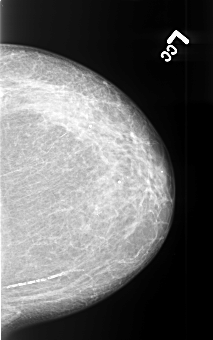

B_3413_1.LEFT_CC

LEFT_CC LINES 4408 PIXELS_PER_LINE 2760 BITS_PER_PIXEL 12 RESOLUTION 50 NON_OVERLAY